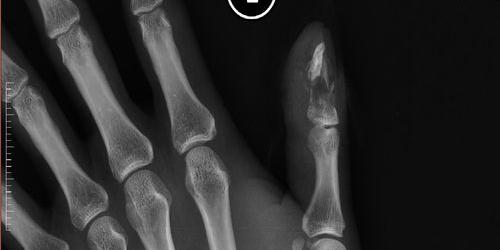

一、工伤轻微骨折一共赔多少万2021年?

一、工伤骨折可以赔多少钱?

工伤、骨折赔偿金额根据伤残鉴定结果确定。工伤、骨折的具体赔偿标准全国统一,具体为:五级伤残为本人16个月工资,六级伤残为本人14个月工资,七级伤残为本人12个月工资,八级伤残为本人10个月工资,九级伤残为本人8个月工资,十级伤残为本人6个月工资。

基于以上可以看出,如果是因工骨折,最合理的是先做相应的工伤鉴定,等待工伤鉴定结果,再按照相应的标准索赔。

二、轻微骨折赔2万5

造成轻微骨折的,应当包括因医疗、误工减少的一切费用,包括医疗费、误工费、护理费、交通费、住宿费、住院伙食补助费和必要的营养费等,由赔偿义务人予以赔偿。具体金额要根据双方协商和当地的收入水平来确定,2.5万是否是合理的赔偿金额。

三、轻微骨折赔1万五合理吗

轻微骨折赔付1.5万是否合理需要根据具体伤情来决定轻微骨折的赔偿标准需要伤残等级鉴定来确定赔偿金额。如果是轻微骨折,还不够伤残。一般除了医药费,最多也就一两万。具体来说,就是要在交警部门出具的事故认定书中,对要承担的责任比例和对方的损害进行赔偿。侵害他人造成人身损害的,应当赔偿医疗费、护理费、交通费、营养费、住院伙食补助费等治疗康复的合理费用以及因误工减少的收入。《工伤保险条例》第一百七十九条侵害他人造成人身损害的,应当赔偿医疗费、护理费、交通费、营养费、住院伙食补助费和其他治疗康复的合理费用,以及因旷工减少的收入。造成残疾的,还应当赔偿辅助器具费用和残疾赔偿金;造成死亡的,还应当支付丧葬费和死亡赔偿金。第一百八十二条侵犯他人人身权益造成财产损失的,应当按照被侵权人所受到的损失或者侵权人所获得的利益给予赔偿;侵权人遭受的损失和侵权人获得的利益难以确定。侵权人与被侵权人未就赔偿数额达成协议,向人民法院提起诉讼的,由人民法院根据实际情况确定赔偿数额。